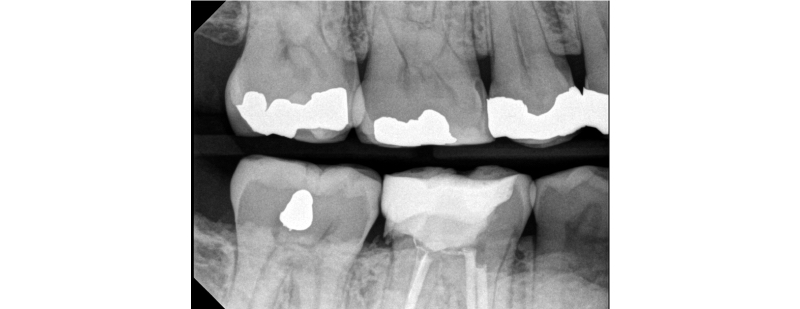

Typically, a post-op bitewing is taken to confirm the proper adaptation of restorative material to tooth structure, mainly when deep margin elevation is used to elevate a margin for indirect restorations. Deep margin elevation can be utilized near the bone with negligible effects on the biologic width when performed in a limited area.